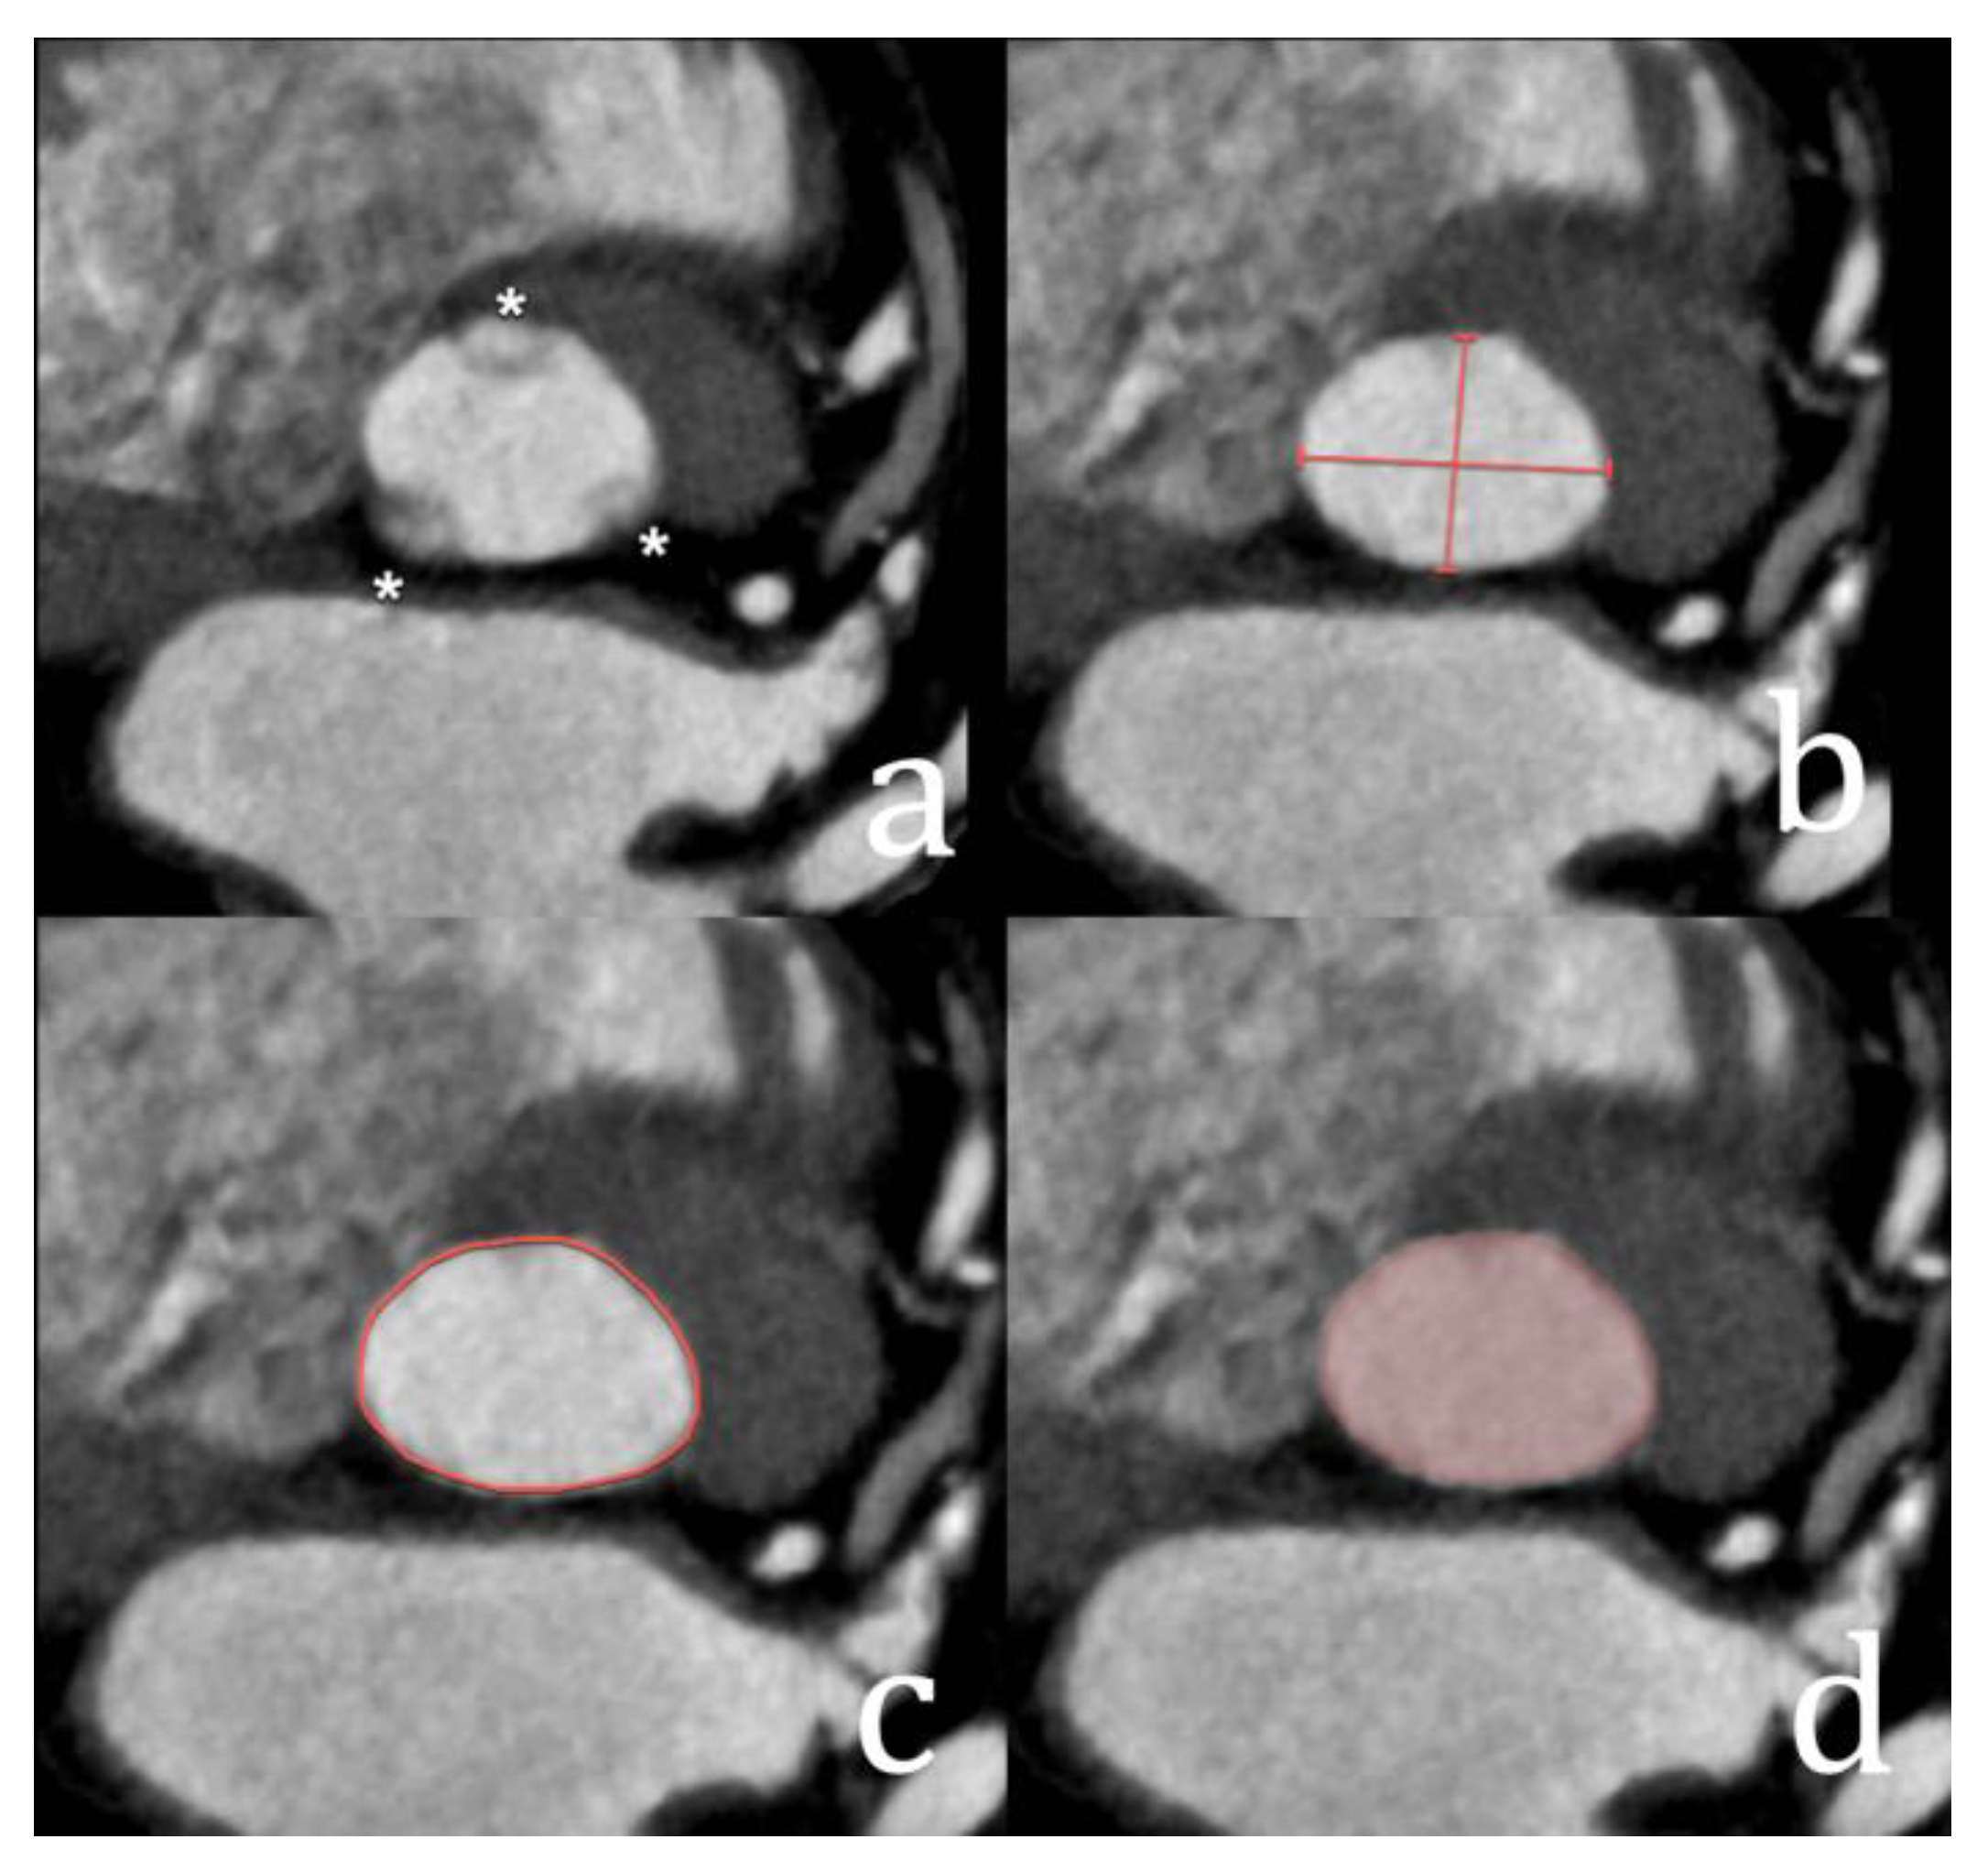

4. Mitral Valve Repair and Replacement